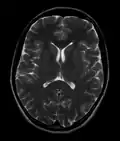

MRI image of the surface of the brain.